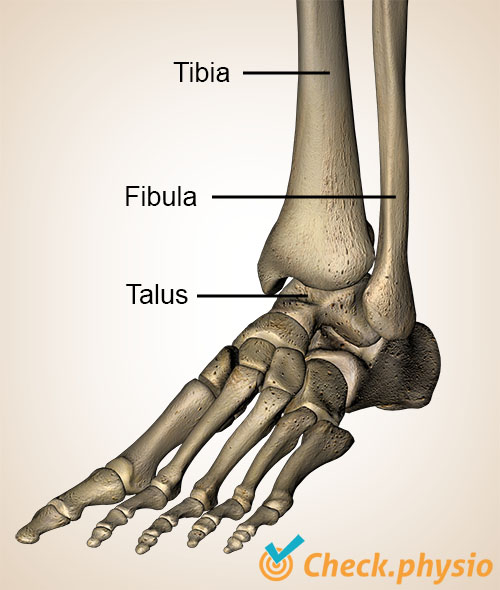

Ankelen består av leggbenet (tibia), leggbenet på utsiden (fibula) og rullebenet (talus). De nedre endene av tibia og fibula danner sammen ankelgaffelen. Rullebenet er omsluttet av disse to beinene. Denne helheten kalles det øvre ankelleddet.